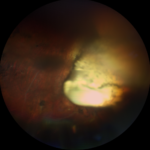

Mon fond d’oeil droit : moins de cicatrices qu’à gauche, assez trouble